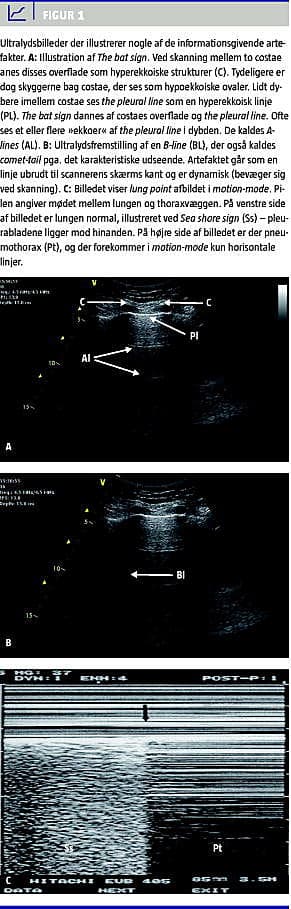

Lungeultralyd starter normalt i zone 1 mellem costa 2 og 3. Først visualiseres de øvre og nedre ribben som kaster hypoekkoiske skygger (Figur) og mellem to ribben ses (hos voksne) 0,5 cm under kostalinien en hyperekkoisk, horisontal linie [4]. Det er the pleural line , der repræsenterer pleura, altså mødet mellem thoraxvæggen og den luftfyldte lunges overflade. Det kaldes the bat sign - de to ribben og pleura danner udseendet af en flagermus i flugt. Fremstillingen af the bat sign bør altid starte enhver lungeultralydundersøgelse, idet det sikrer et korrekt »vindue« med valide informationsgivende artefakter [3, 4].

Nogle af de forskellige informationsgivende tegn i basal lungeultralyd fremgår af Figur 1. For det første ses i den normale lunge lung sliding . Det er et dynamisk tegn, der indikerer pleurabladenes naturlige bevægelse i forhold til hinanden under respirationsbevægelser. Lung sliding bliver tydelig, jo mere man opsøger de kaudale dele af lungen. Lung sliding kan være mere eller mindre udtalt, men giver altid samme vigtige information - de to pleurablade ligger opad hinanden. For at erkende meget små bevægelser kan man supplere med M-mode , hvor man under normale forhold vil opnå et karakteristisk mønster i to dele. Pleural line adskiller to områder som en klar horisontal linje; et område med horisontale linjer øverst på skærmen og nederst et grumset (bølget) område. Et samlet billede, der ligner en kystlinie, deraf tilnavnet Sea Shore Sign , er en alternativ fremstilling af lung sliding . Fravær af lung sliding tyder på PTX, men kan ses ved enhver tilstand med ophævet lungeudfoldelse (massiv atelektase, adhærent pleura, emfysem, simpel apnø og hurtig, overfladisk respiration), og fravær bør derfor kombineres med patientens klinik i øvrigt.

Artefakterne kan deles i to grupper - horisontale og vertikale artefakter. Horisontalt beliggende kan man ofte se en repetition i dybden af the pleural line . Dette kaldes A-lines og ses i den normale lunge. Som skygger af pleural line gentages de med den afstand, der er mellem transducer og pleura [3, 4].

Blandt de vertikale artefakter er B-lines de hyppigste. Kaldes også comet-tails . Dette artefakt starter som alle andre artefakter ved the pleural line og udvisker eventuelle A-lines . Artefaktet er tydeligt defineret og går ubrudt til bunden af UL-billedet, modsat andre ubetydelige vertikale artefakter, der ganske langsomt udviskes i dybden. B-lines bevæger sig ved respirationsbevægelser - synkront med lung sliding , og de er tilstede ved det alveolære interstitielle syndrom. B-lines udspringer fra lungens overflade, og tilstedeværelsen af bare en enkelt B-line udelukker PTX på trods af fravær af lung sliding [3, 4].

Eftersom 98% af alle PTX på liggende patienter findes anteriort og kaudalt, bør undersøgelse for lung sliding indledes i den anteriore zone. Ved fravær af lung sliding anteriort flyttes transduceren mere lateralt under iagttagelse af tilstedeværende lung sliding (vil indikere lungens møde med thoraxvæggen = punktet hvor PTX ophører), hvilket er et 100% specifikt tegn på PTX kaldet lung point [4]. Lungen er måske kun detekterbar under inspiration, hvor den ligger i tæt relation til thoraxvæggen - dette er karakteristisk for en mindre PTX. Derfor er tegnet lung point hyppigst ved PTX, der er svært erkendelig eller ikke synligt på RTX.